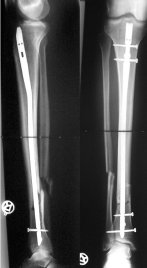

Y finalmente la solución del caso. Evidentemente, como os dije, no voy a explicaros por qué el nº de tornillos y ciertas características técnicas. Esto debe hacerse en un foro profesional. Comprobar que la reducción como os decía no es perfecta, pero la mejora de la alineación y la estabilidad proporciona las condiciones necesarias para una buena curación: